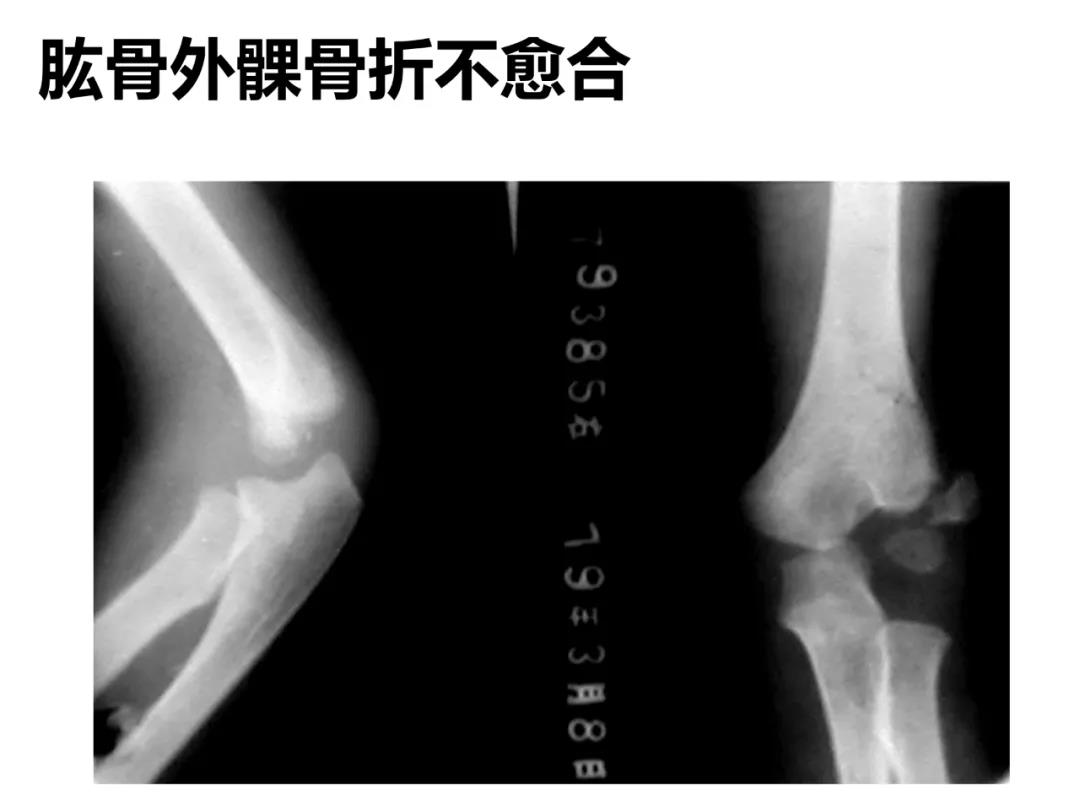

小儿骨科X线片汇总,临床读片宝典!